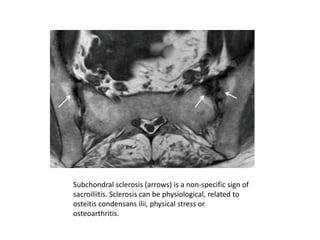

Subchondral sclerosis (arrows) is a non-specific sign of

sacroiliitis. Sclerosis can be physiological, related to

osteitis condensans ilii, physical stress or

osteoarthritis.